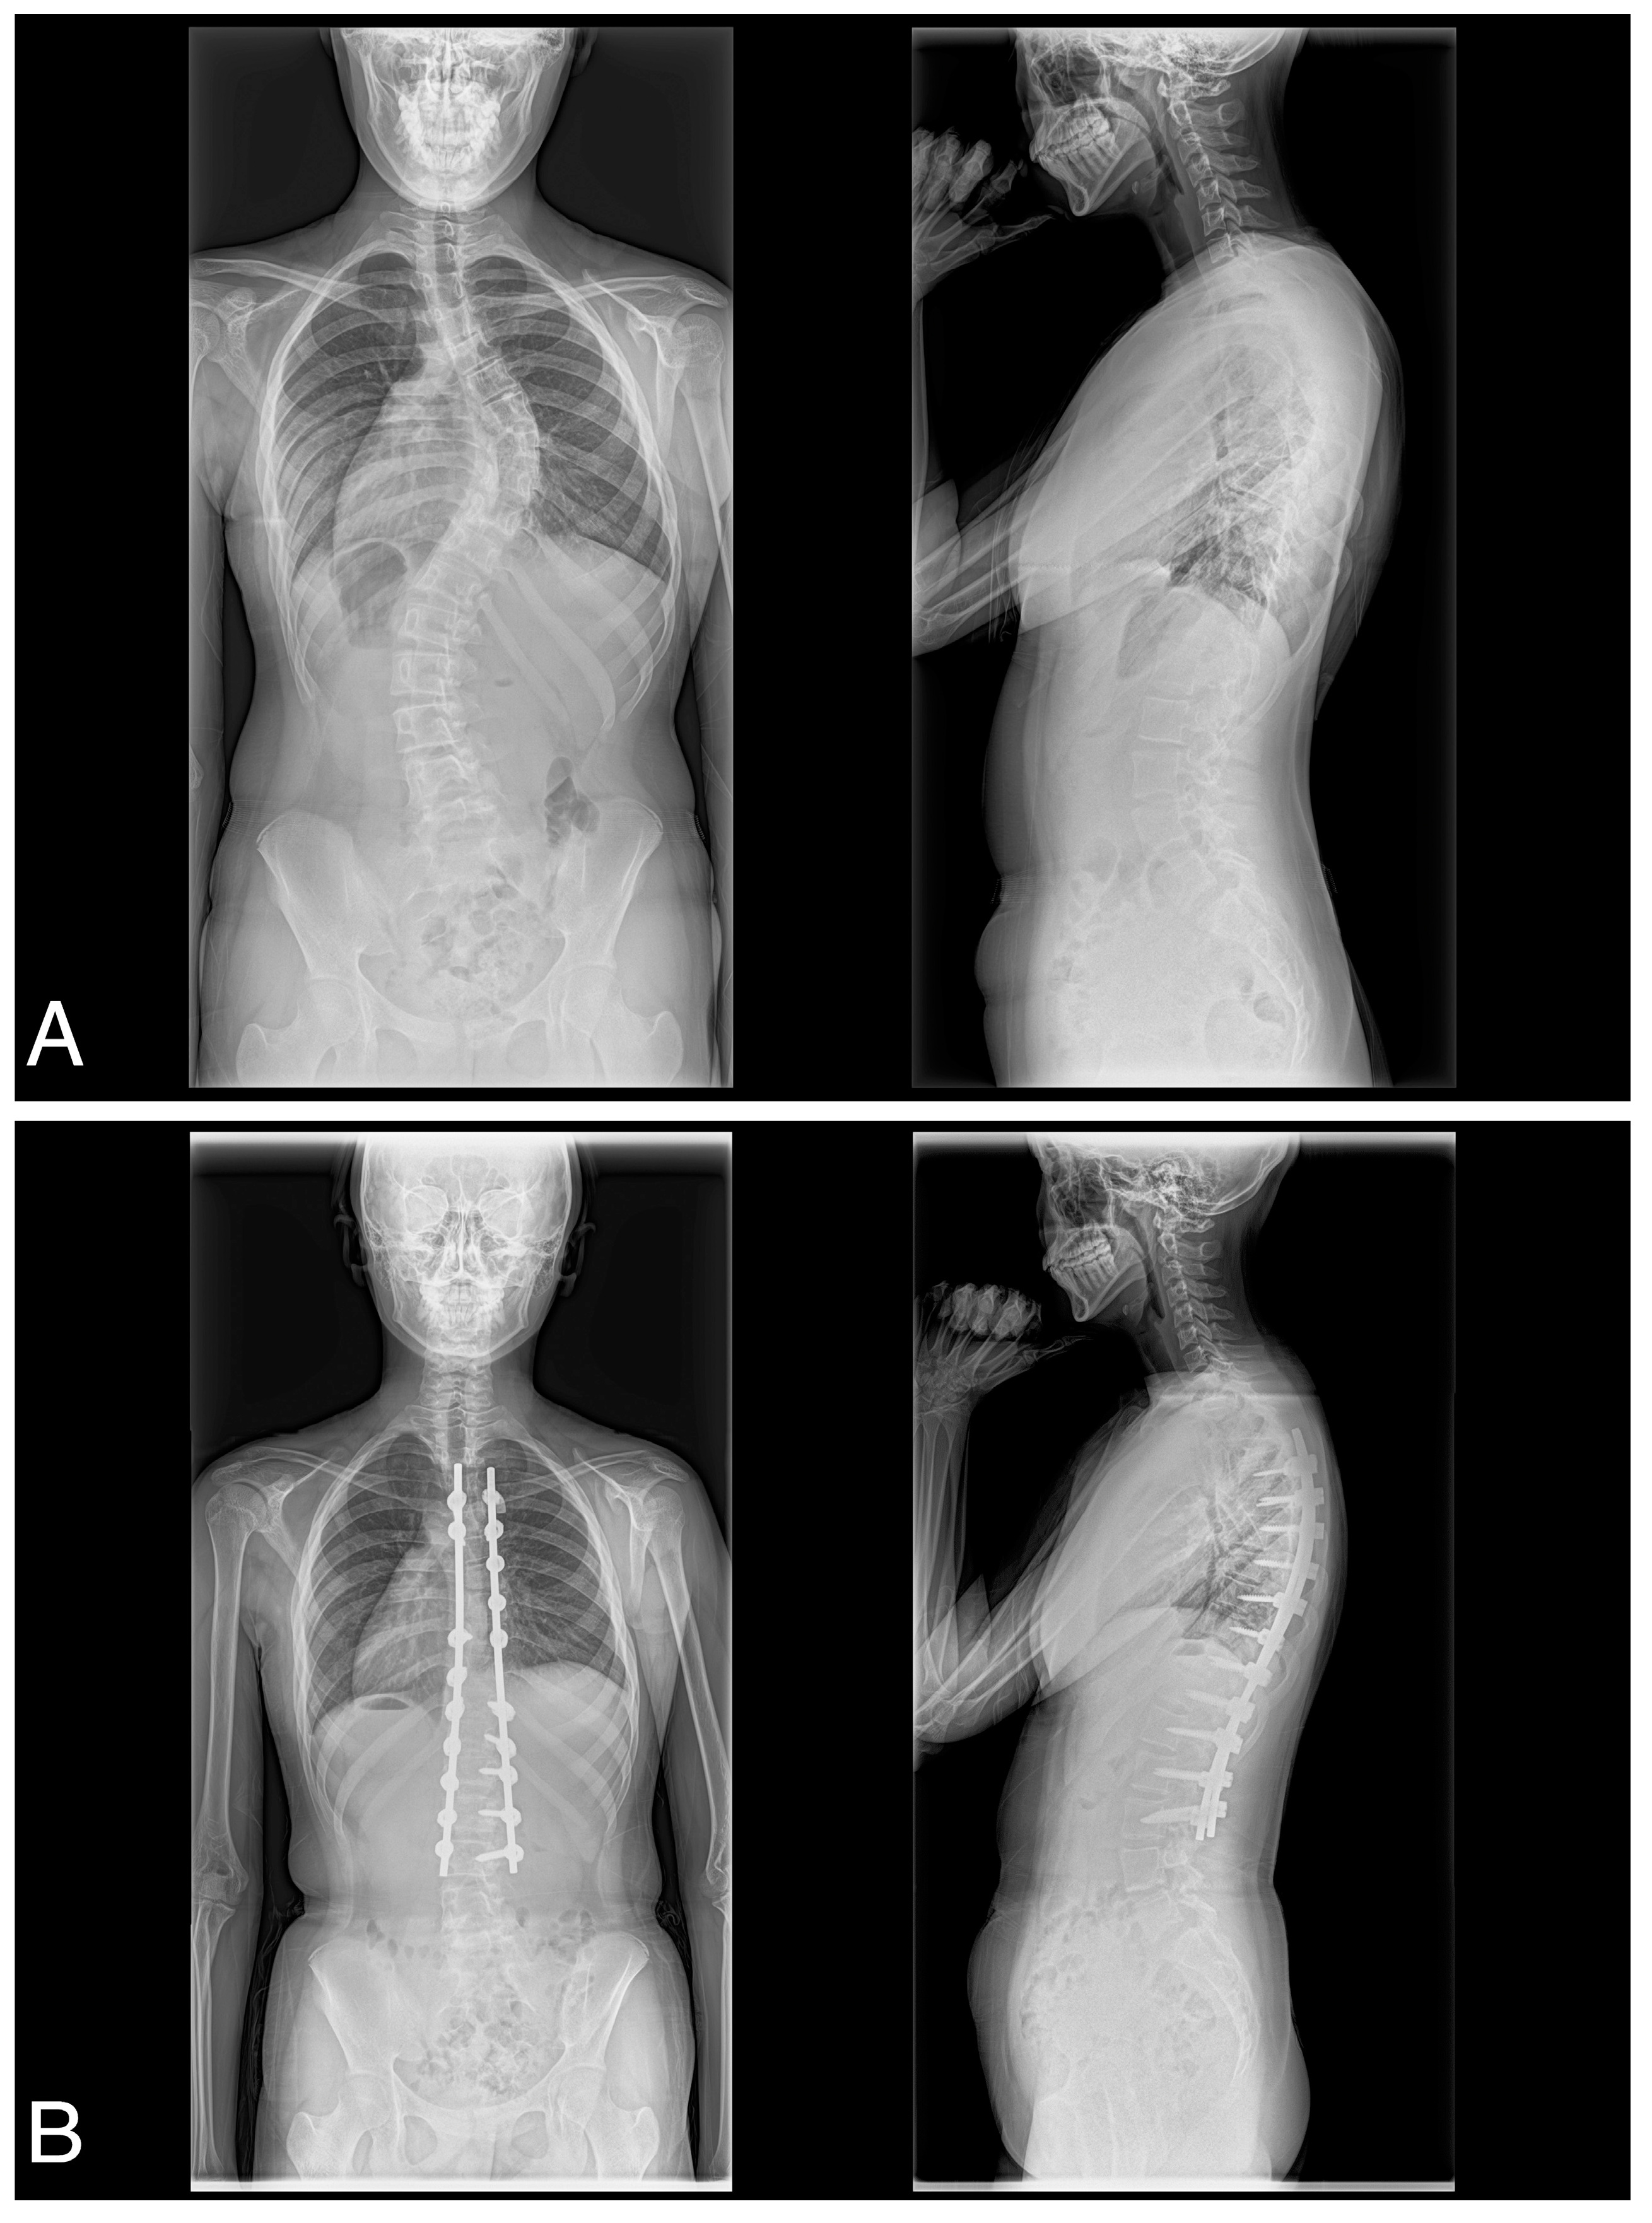

A consecutive series of 41 female patients with AIS with Lenke type 1A (n = 18), 1B (n = 7), 1C (n = 7), 2A (n = 3), 3C (n = 4), 4C (n = 1), or 6C (n = 1) participated in the present study (Table 1). All patients underwent posterior spinal correction and fusion using the 4D anatomical spinal reconstruction technique to correct AIS (Figure 1) [8]. Patients with syndromic, neuromuscular, or congenital scoliosis were excluded. In addition, because the 4D anatomical spinal reconstruction technique was developed to create postoperative anatomical thoracic kyphosis, we have excluded Lenke 5C main thoracolumbar/lumbar AIS curves. All patients were included in the follow up of the study. All patients in this study gave written, informed consent before participating, and the Institutional Review Board of the authors’ associated institutions authorized the study.

Figure 1.

(A) Preoperative posteroanterior and lateral and (B) postoperative posteroanterior and lateral radiographs obtained of a 17-year-old female with Lenke type 1C scoliosis.